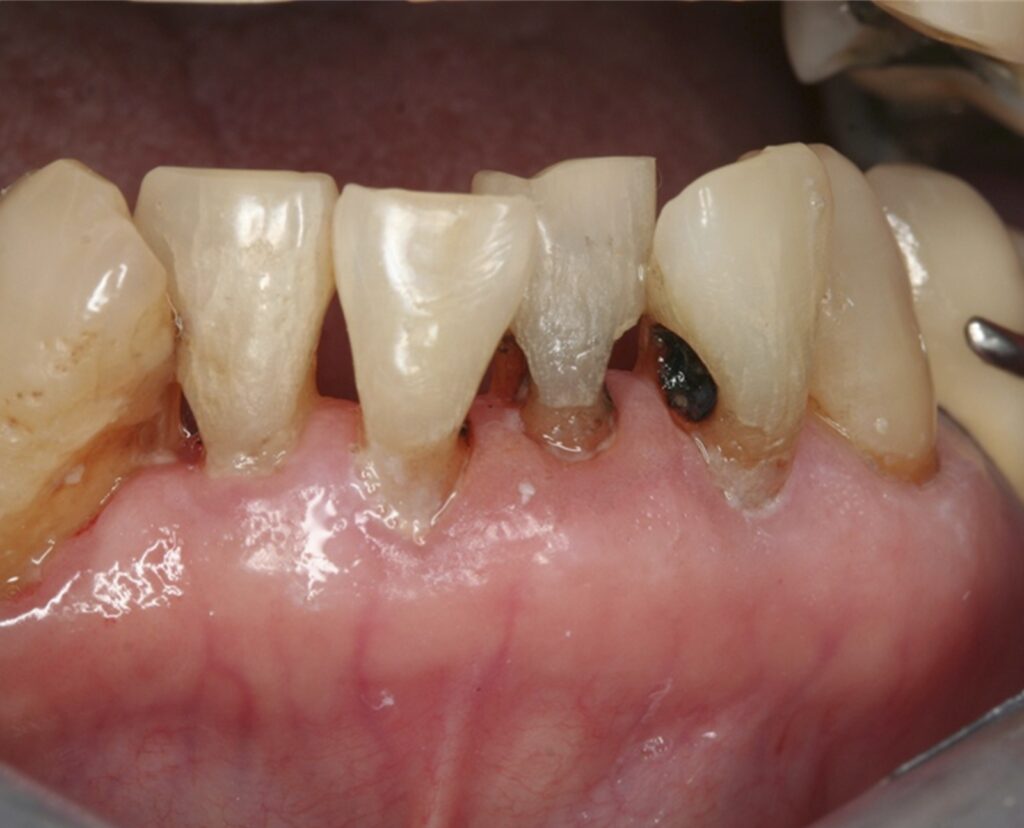

Nhược điểm cố hữu của SDF là các tổn thương sâu răng sẽ bị ố đen sau khi bôi. SDF ngăn chặn sự tiến triển của sâu răng bằng cách hình thành một lớp cứng, đen, không thấm nước trên bề mặt răng và có khả năng chống sâu răng.